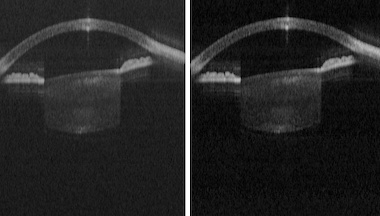

In trials on the eye of a volunteer, the new platform captured full-eye scans from the cornea to the retina at 25 and 50 kHz, and obtained biometric information such as the axial eye length and anterior chamber depth with axial precision comparable to commercial OCT systems, according to the team.